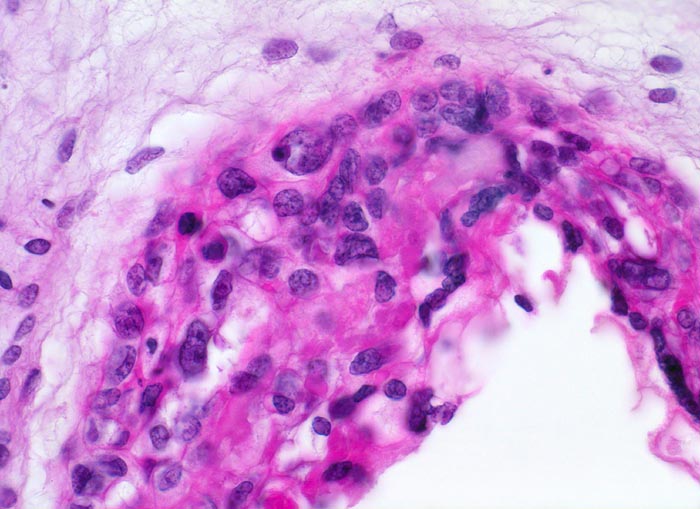

Makroskopisch ist die Plazenta deutlich grösser als erwartet für das Schwangerschaftsalter. Sie ist diffus von bis 2cm grossen Zottenblasen durchsetzt, welche nach Kollaps jedoch der makroskopischen Entdeckung entgehen können. Beim Aufschwemmen in Flüssigkeit entfalten sich die Blasen wieder. Mikroskopisch sind die Zotten aufgrund einer grobblasigen pseudozystischen Hohlraumbildung im Zottenstroma überwiegend grosskalibrig. Im Zottenstroma sind nur ganz vereinzelt Kapillaren nachweisbar. Im Gegensatz zu hydropisch geschwollenen Zotten im Sinne eines Regressionsphänomens zeigen die Zotten bei Blasenmole zusätzlich eine zirkumferentielle Hyperplasie von Synzytio- und Zytotrophoblast mit fakultativer Zellatypie. Bei herdförmiger Mole (> 3725) sind diese Veränderungen nur in einem Teil der Plazentarzotten ausgeprägt.

• Überschiessend proliferiertes Trophoblastepithel, teils in der gesamten Zirkumferenz der Zotten mit deutlichen Kernatypien. Kein Embryo.